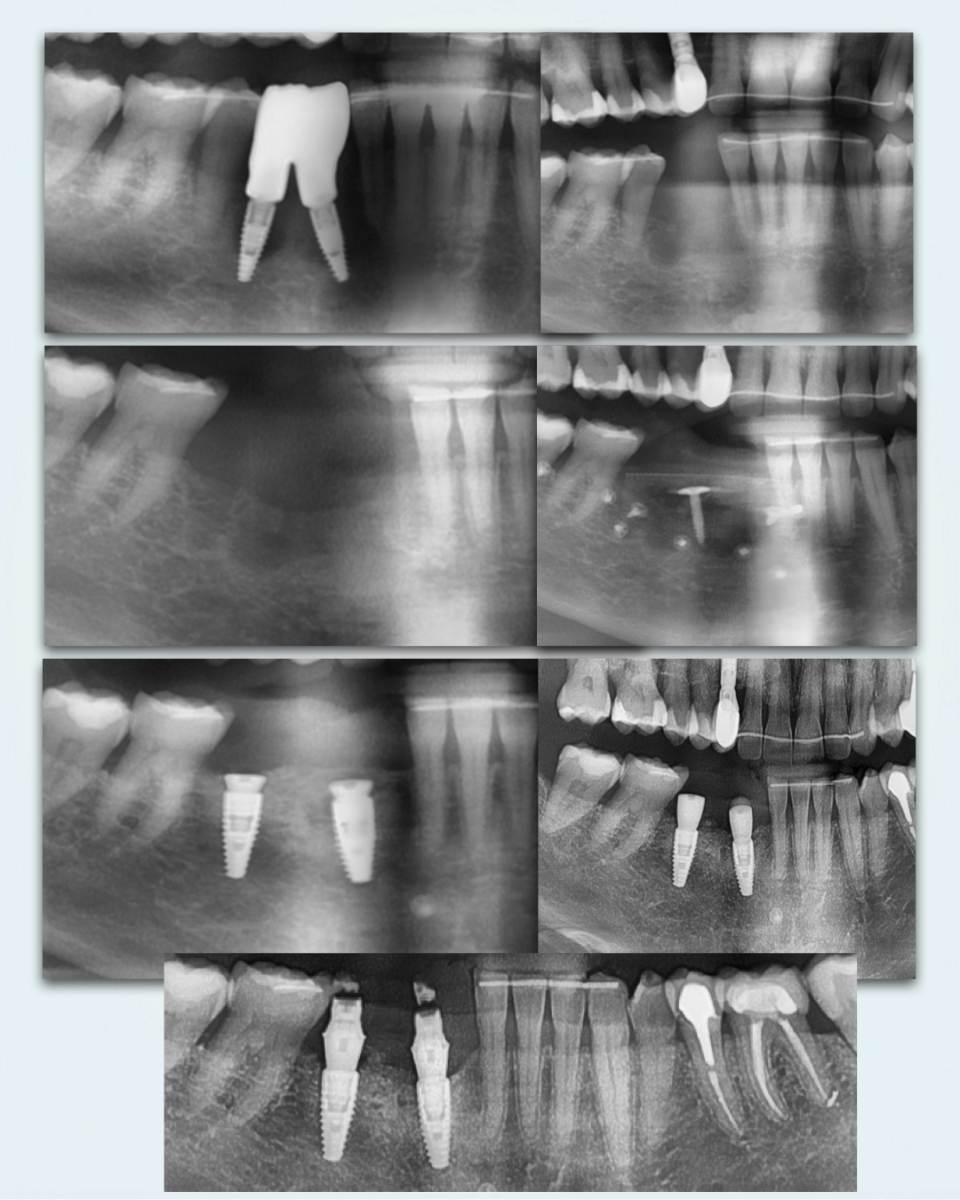

stommm Опубликовано 28 сентября, 2024 Поделиться Опубликовано 28 сентября, 2024 Всем доброго времени суток. История длиною в 2 года 9 месяцев. Ортопед Залим Иругов, техник Виталий Шамин. Приятного просмотра) 10 1 1 Ссылка на комментарий

stommm Опубликовано 29 сентября, 2024 Автор Поделиться Опубликовано 29 сентября, 2024 1 час назад, Aquarius сказал: Браво!! Блестящая работа, доктор!! Скажите , донорские зоны такого масштаба ведёте под капой? Спасибо не пользуюсь каппами. Композитная повязка и швы 9 минут назад, Тимур86 сказал: Крутяк! Фото сочные. Зачем тент под титановую мембрану? Спасибо что бы мембрану было проще по высоте стабилизовать. Но в итоге он встал ниже чем хотелось, лунки плохо зажили. Так что не особо помог Ссылка на комментарий

stommm Опубликовано 29 сентября, 2024 Автор Поделиться Опубликовано 29 сентября, 2024 8 минут назад, Женька сказал: чья сетка и чем шили уже спрашивали?) Сетка вроде Пенза. Винты (кроме тентового) точно их. Швы 1 птфэ, остальное эльмонк 6-0 или моноквик 6-0. Может ещё 7-0 пдо где-то был, не помню. 2 1 Ссылка на комментарий